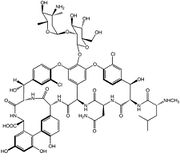

| 15:42 6 sep 2011 | Vancomicina.JPG (archivo) |  |

28 KB | 1 | |